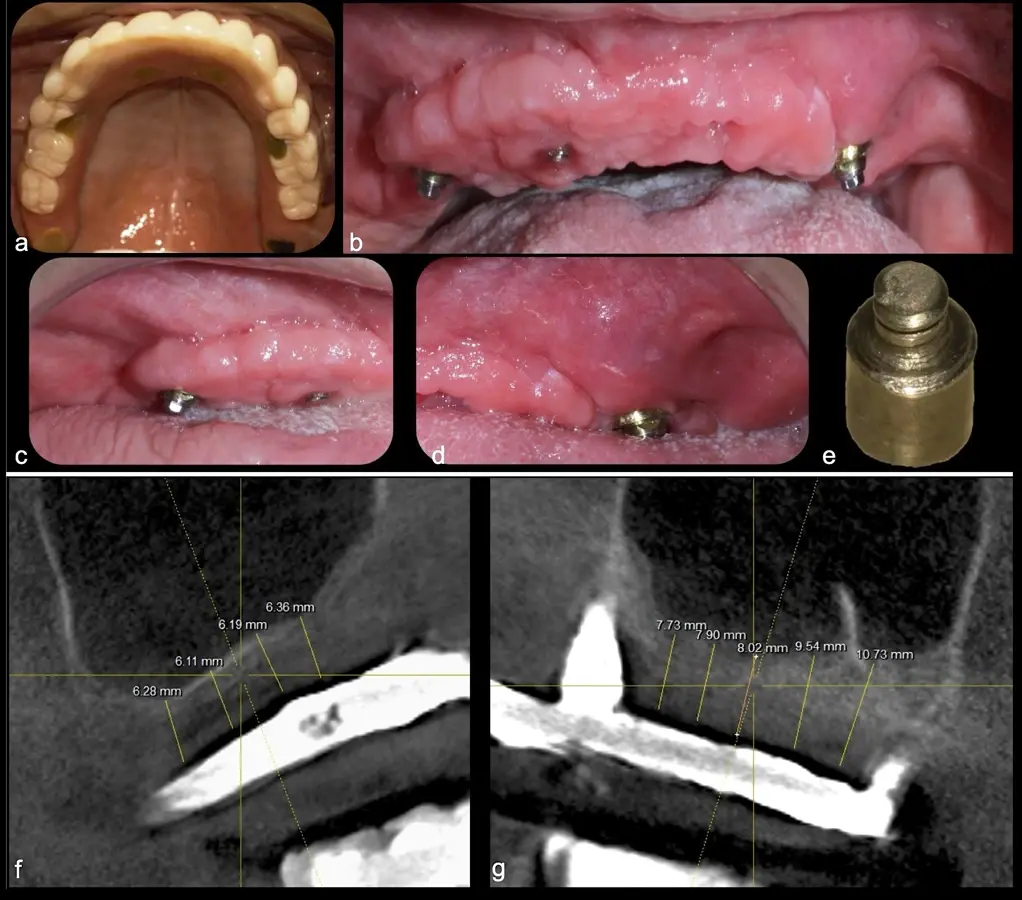

El levantamiento de piso de seno maxilar es una técnica quirúrgica aceptada previa o simultáneamente a la colocación de implantes dentales. La mayor evidencia científica refiere que si se tiene entre 0 -7 mm de altura ósea se debe realizar la elevación sinusal junto con injertos óseos; y a partir de los 8 mm, se hace más predecible la colocación simultánea de implantes dentales.1-3

Aunque esta técnica es predecible, la perforación de la membrana sinusal es la complicación intraoperatoria más común, con una prevalencia de hasta el 58.3%.4 Existen también otras complicaciones reportadas, como hemorragias asociadas a la lesión de la anastomosis arterial en el área de la pared lateral del seno maxilar.5-8

Frente a esta dificultad, a principios de este siglo se utilizó por primera vez un modelo comercial de piezoeléctrico en elevaciones sinusales demostrando su capacidad de corte sólo de tejidos duros y reduciendo el daño a la membrana sinusal, la cual cuenta con un espesor promedio de 1.13mm.10-12

El piezoeléctrico además presenta otras ventajas como una baja emisión de ruidos, vibraciones mínimas, producción de virutas óseas pequeñas, visibilidad intraoperatoria mejorada, y requiere de una incisión ósea controlada8. A nivel local, aumenta elementos pro-formadores de tejido óseo y disminuye algunas de las citoquinas proinflamatorias y resortivas en el hueso.13 Sus movimientos vibratorios durante el corte estimulan el metabolismo celular y aceleran la regeneración ósea. Además, las moléculas de oxígeno que se liberan tienen un efecto antiséptico.14,15 Por todo ello, se ha reportado que reduce la tasa de perforaciones de la membrana sinusal, el sangrado y el trauma en el área antral.16-18,19

Estudios de síntesis bibliográficas con meta-análisis han descrito que el uso de instrumentos rotatorios convencionales está asociado a una tasa de perforación del 24% y con los dispositivos piezoeléctricos a un 8%, con una diferencia clínica y estadísticamente significativa entre ambas modalidades.17